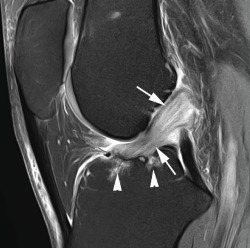

Los hallazgos de RM en las roturas parciales del LCA consisten en un aumento de la señal intrasustancial, defectos focales, distorsión y atenuación de fibras o una orientación anormal del ligamento(1,16)(Figuras 4 y 5). El diagnóstico es más sencillo en fase aguda, por la presencia de signos secundarios con edema y derrame articular. La principal dificultad diagnóstica con RM en la fase aguda consiste en diferenciar roturas parciales de alto grado de completas(1,16).

Figura 4. Rotura parcial del fascículo anteromedial (AM) del ligamento cruzado anterior (LCA) con formación de pequeño ganglión en la escotadura intercondílea. Corte oblicuo coronal (A) y axial (B) de resonancia magnética (RM) potenciados en densidad protónica con supresión grasa que muestran una rotura del fascículo AM (flechas). Fascículo posterolateral normal (cabezas de flecha).

El diagnóstico es más complicado en la fase crónica, especialmente en roturas parciales con resinovialización y cicatrización con fijación al ligamento cruzado posterior (LCP) adyacente. Estas lesiones se pueden confundir con frecuencia con lesiones parciales de bajo grado o con un ligamento normal en la RM. En la exploración clínica estos pacientes muestran generalmente menor laxitud con tope firme(1).

Figura 5. Rotura parcial del fascículo posterolateral (PL) del ligamento cruzado anterior (LCA). Corte oblicuo coronal (A) y axial (B) de resonancia magnética (RM) potenciados en densidad protónica con supresión grasa que muestran una rotura completa proximal del fascículo PL (flechas). Fascículo anteromedial normal (cabezas de flecha).

Ocasionalmente, en la roturas parciales proximales del fascículo AM, el fascículo se dobla en sentido anterior con un aspecto que se define como lesión cíclope o en badajo de campana. Esta lesión puede ser responsable del bloqueo articular, simulando clínicamente un desgarro en asa de cubo(1).